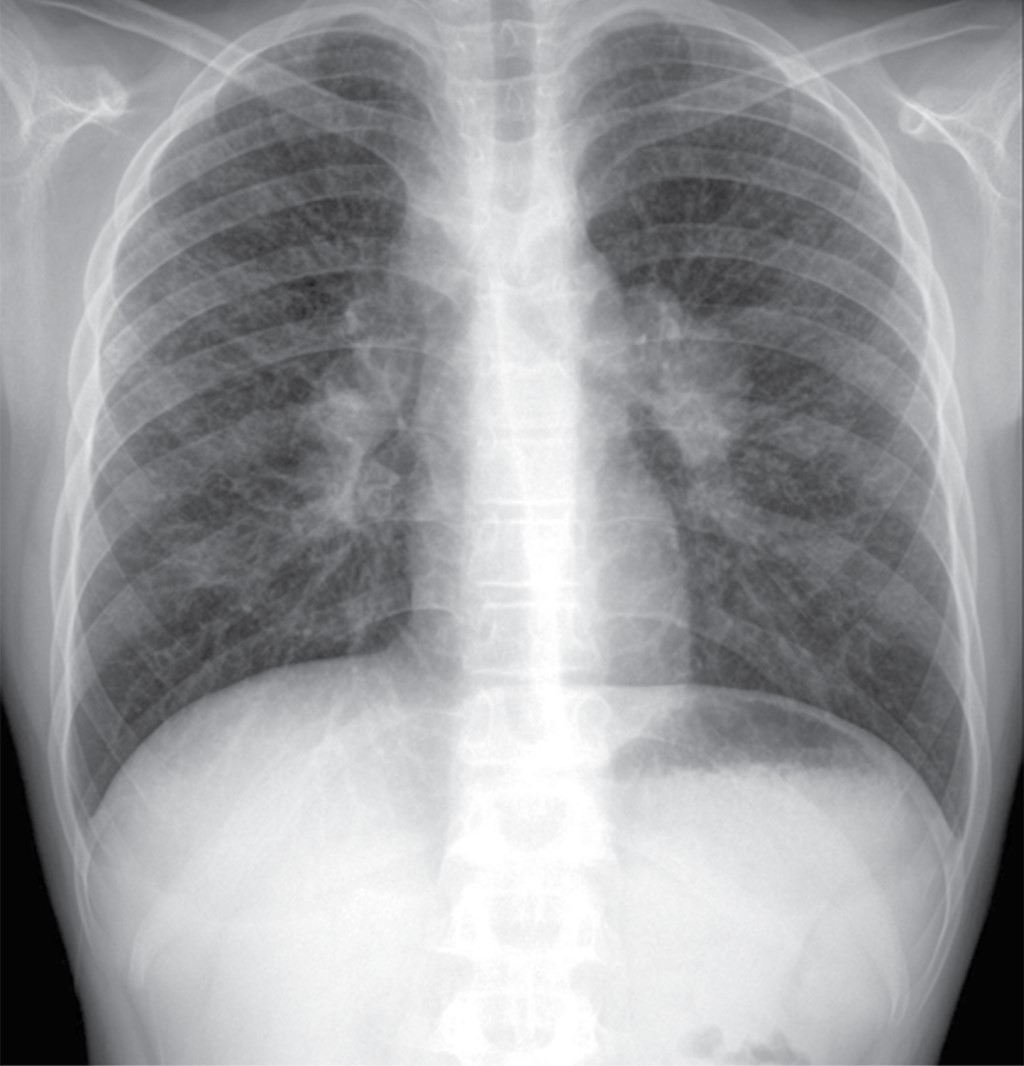

La radiografía de tórax inicial mostró: ensanchamiento parahiliar bilateral por crecimientos ganglionares y un patrón intersticial fino bilateral y difuso, casi simétrico con algunas imágenes micronodulares bilaterales (Figura 1).

La radiografía de tórax mostró ensanchamiento mediastinal y un patrón intersticial grueso a expensas de intersticio perilobulillar bilateral y difuso, casi simétrico con algunas imágenes nodulares también difusas (Figura 9). En la TACAR contrastada se corrobora el patrón intersticial perilobulillar con nódulos difusos con discreto predominio subpleural así como zonas de atelectasia bilateral subpleurales y en lóbulo medio (Figura 10). En la ventana mediastinal se demuestran crecimientos ganglionares paratraqueales de predominio derecho, en ventana aortopulmonar y axilar bilateral. A nivel abdominal lesiones nodulares hipodensas múltiples hepatoesplénicas sugestivas de granulomas (Figura 11). Se realizó biopsia de piel en cara, la cual mostró dermatitis granulomatosa epitelioide no caseificante, compatible con sarcoidosis (Figura 12).

La radiografía de tórax es anormal en 90% de los casos. Los dos hallazgos más característicos son la linfadenopatía mediastinal bilateral acompañada de enfermedad intersticial nodular del pulmón, éstos sirven para la estadificación de la enfermedad,5,8 siendo la TACAR la herramienta más valiosa para el diagnóstico (Tabla 1).

Las adenopatías paratraqueales bilaterales e hiliares son las más comunes. Los patrones radiológicos parenquimatosos más comunes son las opacidades reticulonodulares (90%) en las zonas superiores del pulmón, afección alveolar y fibrosis pulmonar. El patrón miliar es raro a cualquier edad.1,5,8

Nuestros casos se clasifican en el estadio II, ya que en la TACAR se detectó adenopatía hiliar bilateral con infiltrados pulmonares (Tabla 1).